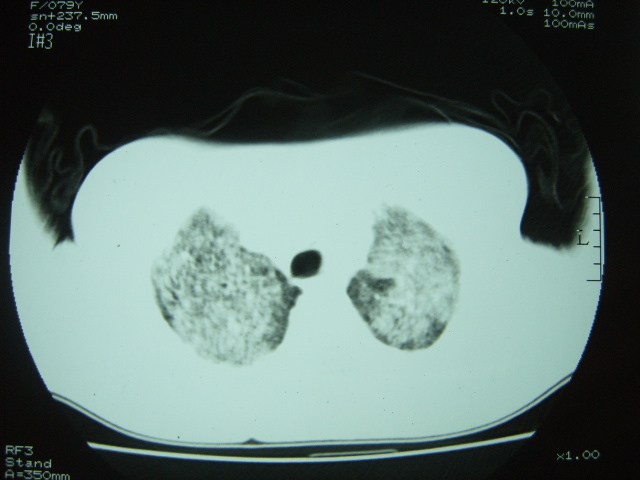

标题: CT7574:双肺病变,请会诊。急!急!

女 79岁,今日高烧,无咳嗽及痰,是否粟粒结核还是?

双肺弥漫性病变,以肺间质改变为主,

胸内小结节部分融合成片,边缘模糊,

双肺弥漫小结节状高密度,部分融合,边界不清(因为不是hrct,可能为部分容积效应引起),肺门纵隔内未见肿大淋巴结影。无胸腔积液。

考虑:急性血型播散型肺结核,不除外过敏性肺炎;建议治疗后复查。

双肺弥漫性结节影,双肺上叶为著.纵隔内可见一肿大淋巴结影,密度较高.支持急性血行播散型肺结核.双侧少量胸腔积液.

双肺弥漫基本均匀分布的小结节状高密度影,部分融合。支持急性血性播散性肺结核。

两肺弥漫分布小结节状高密度影,其大小,密度一致,分布均匀,并可见与后胸壁平行的弧状影

诊断:两肺急性血型播散形肺结核